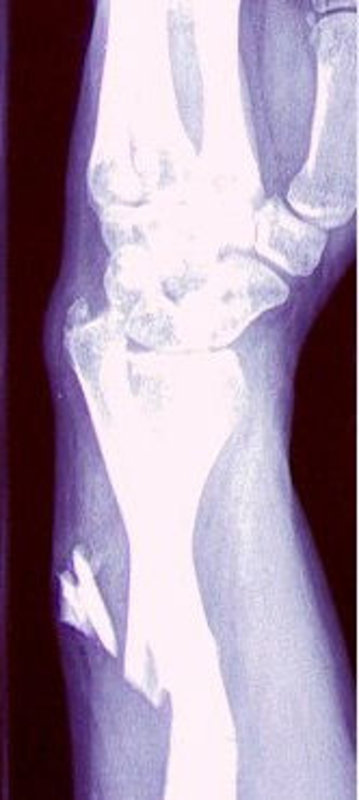

So ungefähr sieht's in unserem Redakteur Laszlo Strzoda aus.

Den hätte ich Euch auch gern geschickt. Leider wurde mir bei einem Polizeieinsatz der Arm zweimal gebrochen. Und Überraschung: Mit dem zweiten tippt es sich schlechter. Außerdem habe ich dann im Krankenhaus erst einmal Morphium gegen die Schmerzen bekommen. Drogenliberalisierung finde ich politisch ja gut, aber bei mir hat das erst mal die Pforten der Wahrnehmung geschlossen. … ich bin eben nicht Aldous Huxley.

Nein, das nicht. Aber ich hatte Glück im Unglück. In der Nähe waren Demo-Sanitäter, die haben sich dann meiner angenommen, haben einen Dreiecksverband angelegt und den gebrochenen Arm geschient. Danach bin ich ins Krankenhaus Lüneburg getrampt, wo ich geröntgt und ambulant behandelt wurde.

Zunächst einmal, dass ich wohl, je nach dem, was die Folgeuntersuchungen ergeben werden, sechs bis zwölf Wochen mehr oder weniger ausgeschaltet bin. Ich werde Ende der Woche eine Operation über mich ergehen lassen müssen. Es kann sein, dass noch weitere Eingriffe nötig werden.